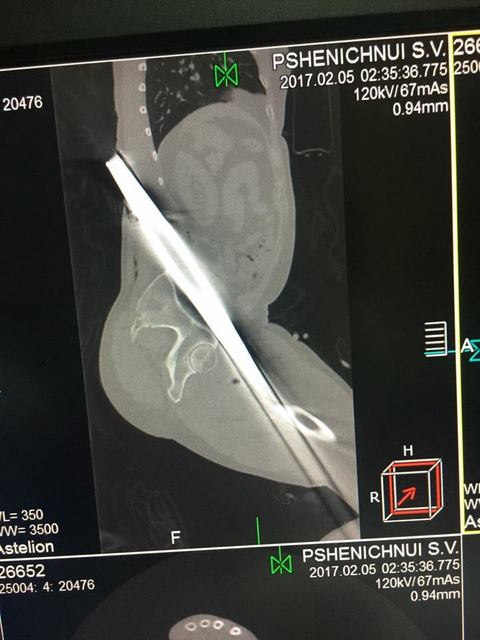

Заведующий приемно-диагностического отделения больницы имени Мечникова Петр Давыденко рассказал, что металлический профиль буквально насквозь проткнул мужчину.

«Итог: инородное тело левой голени, левого бедра, левой половины таза, левой половины поясничной области, открытый многооскольчатый перелом верхней трети левой большеберцовой кости, травматический шок», — отметил врач.

Первую медицинскую помощь пострадавшему оказали в Царичанке, после чего мужчину доставили в Мечникова. Осмотр немедленно провели дежурные травматологи, урологи, хирурги и нейрохирурги. Провели операцию по удалению инородного тела, ПХО ран, лапароцентез, а также объемное переливание препаратов крови.

Пострадавшего госпитализировали в реанимационное отделение. По словам Петра Давыденко, внутренние жизненно важные органы и магистральные сосуды чудом не повреждены. Состояние пациента тяжелое, но стабильное.